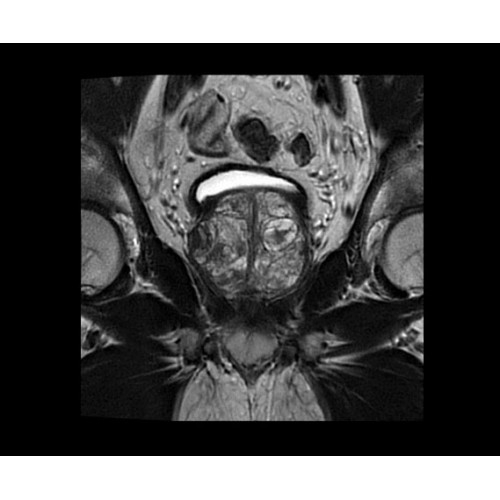

• BodyWorks — для визуализации абдоминальной и тазовой областей, подстраиваясь под запросы пользователя с учетом любых типов пациентов.

• OncoWorks — клинические приложения для обработки и визуализации анатомических и морфологических данных, специфичных для каждого типа онкологических образований.